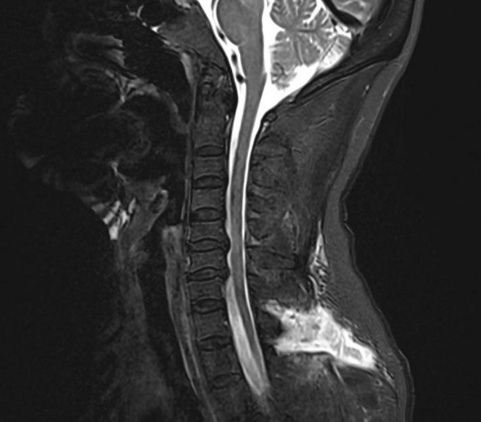

为精准定位“漏点”,刘伟主任医疗团队为靳女士安排了腰椎穿刺测压和全脊柱核磁水成像检查。结果证实了诊断:颅压低至68mmH₂O(正常约为80-180mmH₂O),进一步行腰大池CT造影剂清晰地显示,漏口就隐藏在颈7/胸1和胸1/2这两个节段。

术前术后影像对比

术前影像